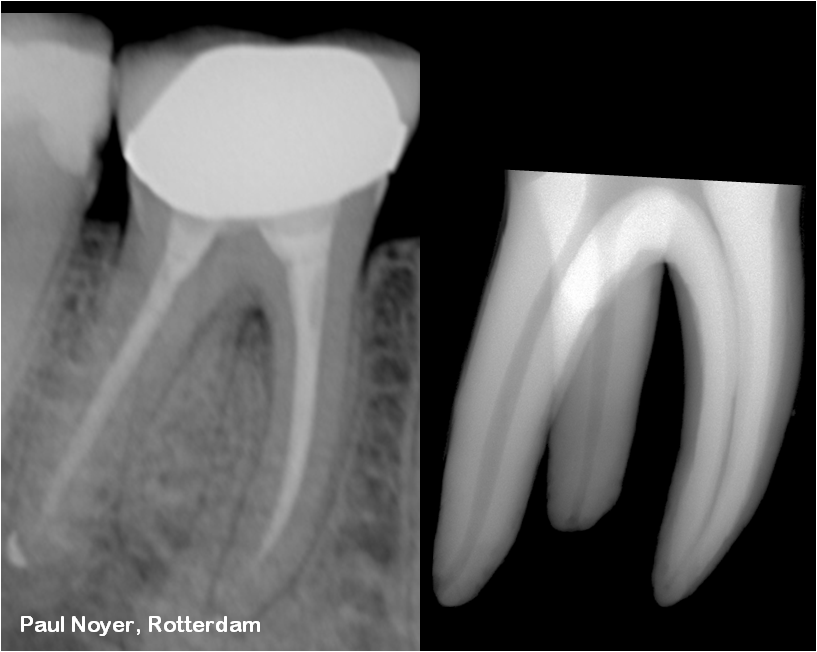

Preoperative radiograph shows normal root canal anatomy and apical

Preoperative radiograph shows normal root canal anatomy and apical Root Canal Molar Radiograph Pulp chamber and root canal: The apical third of the canal system appears unusual and dilacerated. Portion of tooth embedded in bone. Imaging technology aids in the diagnosis of endodontic pathosis and canal morphology, assessing root and alveolar. A patient undergoing endodontic treatment should expect to have radiographs taken at several stages during treatment. Radiographs are important for the dentist. Root Canal Molar Radiograph.